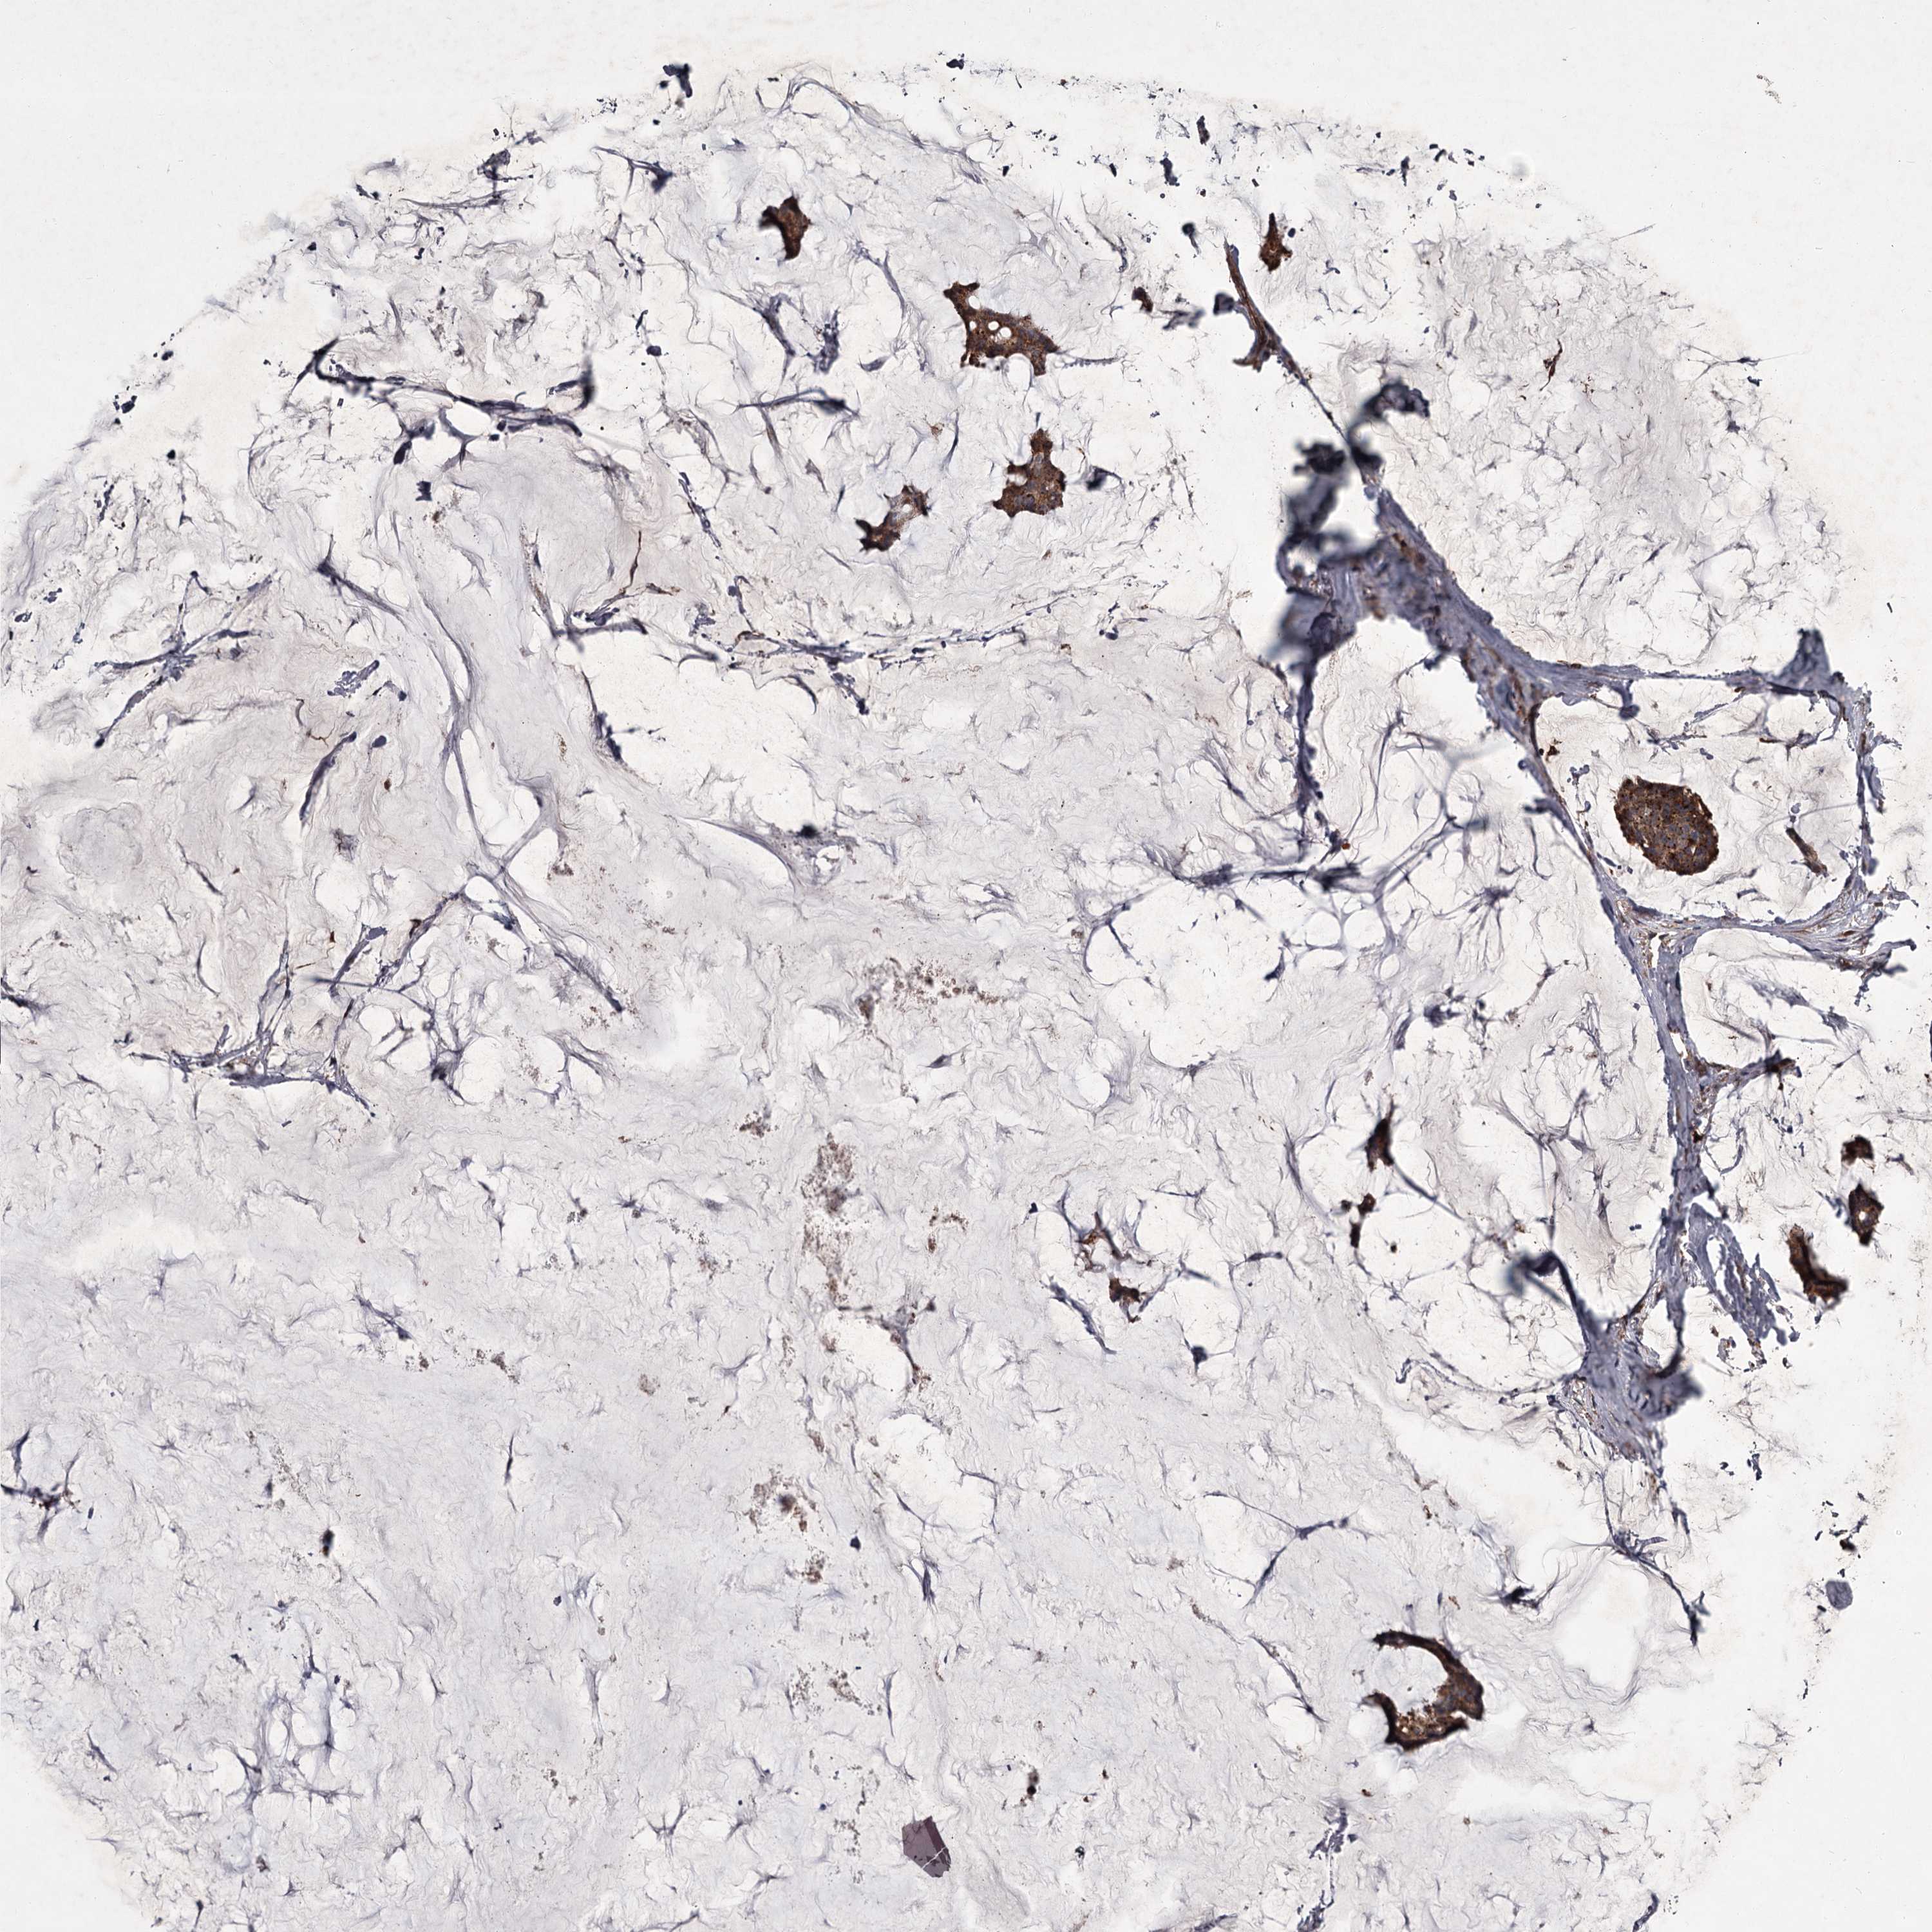

CANCER BREAST CANCER Show tissue menu

BRCA TCGA BRCA VALIDATION PROTEIN EXPRESSION

Breast cancer

Human cancer

UNC93B1 is potential prognostic, high expression is unfavorable in Breast Invasive Carcinoma (TCGA)